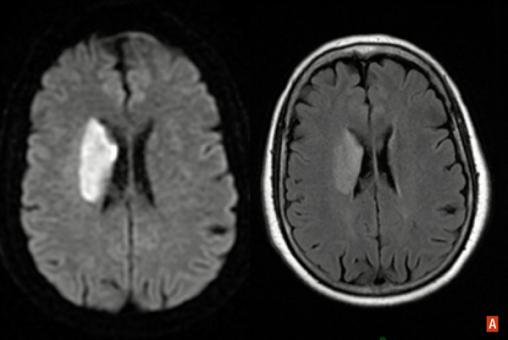

Infarctus sylvien profond droit : hypersignal, IRM en séquence de diffusion à gauche et FLAIR à droite.